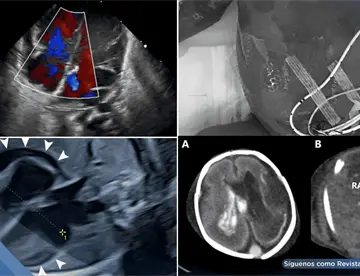

<content:encoded><![CDATA[<div><img src="https://blob.medicinaysaludpublica.com/images/2026/05/04/sacs-20--1089-300e16cb-focus-0-0-360-276.webp" alt="Hemorragia pulmonar por trombosis de vena cava simula sangrado digestivo en paciente en hemodiálisis " title="Hemorragia pulmonar por trombosis de vena cava simula sangrado digestivo en paciente en hemodiálisis "></div><p>Un hombre de 45 años con enfermedad renal crónica en hemodiálisis ingresó con aparente hematemesis e inestabilidad hemodinámica. Aunque el cuadro sugería un <strong><a href='https://medicinaysaludpublica.com/tags/sangrado/28213' target='_blank'>sangrado</a></strong> gastrointestinal superior, los estudios endoscópicos fueron inconclusos.&nbsp;</p>

<p>La tomografía torácica y la <strong><a href='https://medicinaysaludpublica.com/tags/broncoscopia/54407' target='_blank'>broncoscopia</a></strong> confirmaron una hemorragia pulmonar secundaria a trombosis de la vena cava superior, evidenciando un diagnóstico poco frecuente que puede imitar una emergencia digestiva.</p>

<h1><strong>Evaluación inicial: Sin evidencia de <strong>sangrado</strong> digestivo activo</font></strong></h1>

<p>La endoscopia digestiva alta mostró várices esofágicas pequeñas y gastropatía erosiva, pero sin <strong>sangrado</strong> activo que justificara la gravedad del cuadro. Este hallazgo obligó a ampliar el enfoque diagnóstico, considerando causas no gastrointestinales.</p>

<p>En este contexto, la tomografía computarizada de tórax reveló un hallazgo clave: trombosis de la vena cava superior con abundante circulación colateral mediastínica. Además, se evidenciaron áreas de consolidación alveolar compatibles con hemorragia pulmonar y un derrame pleural derecho.</p>

<strong>Confirmación diagnóstica</font></strong></h2>

<p>La <strong>broncoscopia</strong> fue determinante al identificar <strong>sangrado</strong> activo en el árbol bronquial derecho con presencia de coágulos adheridos, confirmando que la fuente del <strong>sangrado</strong> era respiratoria y no digestiva.</p>

<p>Este fenómeno explica cómo la sangre proveniente del tracto respiratorio puede ser deglutida o expulsada durante episodios de arcadas, simulando una hematemesis y generando confusión diagnóstica.</p>

<strong>Claves fisiopatológicas: Cuando la trombosis venosa desencadena hemorragia</font></strong></h2>

<p>La trombosis de la vena cava superior genera aumento de la presión venosa proximal, lo que favorece la formación de vasos colaterales frágiles en el mediastino y árbol bronquial. Estos vasos pueden romperse y provocar hemorragia pulmonar.</p>

<p>En pacientes con enfermedad renal crónica, este riesgo se incrementa debido a la disfunción endotelial, el estado protrombótico y el uso repetido de accesos vasculares, factores que contribuyen al daño vascular y la formación de trombos.</p>

<strong>Desafío diagnóstico en pacientes críticos</font></strong></h2>

<p>Este caso pone en evidencia una trampa clínica relevante: la hemorragia pulmonar puede simular un <strong>sangrado</strong> digestivo, especialmente en pacientes críticos o intubados.&nbsp;</p>

<p>De hecho, hasta el 15 % de los casos sospechosos de <strong>sangrado</strong> gastrointestinal superior no tienen una fuente identificable en la endoscopia inicial.</p>

<p>La ausencia de signos clásicos del síndrome de la vena cava superior, como edema facial o circulación colateral visible, contribuyó a retrasar el diagnóstico correcto.</p>

<strong>Manejo y evolución: enfoque multidisciplinario</font></strong></h2>

<p>El paciente fue manejado en unidad de cuidados intensivos con soporte ventilatorio, hemodinámico y evaluación por neumología, hematología y radiología intervencionista. La anticoagulación fue diferida inicialmente debido al alto riesgo hemorrágico, mientras se planificaba una intervención dirigida como trombectomía.</p>

<p>Tras estabilización clínica, el paciente mostró mejoría progresiva y fue trasladado fuera de cuidados intensivos.</p>

<strong>Implicaciones clínicas: ampliar el diagnóstico diferencial salva vidas</font></strong></h2>

<p>Este caso, según Oscar Molina Lizama et al., resalta la importancia de considerar causas extraintestinales en pacientes con sospecha de <strong>sangrado</strong> digestivo cuando los hallazgos endoscópicos no son concluyentes. En particular, en pacientes en hemodiálisis con antecedentes de accesos venosos centrales, la trombosis de la vena cava superior debe incluirse dentro del diagnóstico diferencial.</p>

<p>La integración de estudios de imagen y <strong>broncoscopia</strong> resulta fundamental para identificar la fuente real del <strong>sangrado</strong>, evitar procedimientos innecesarios y dirigir un tratamiento oportuno y específico.</p>